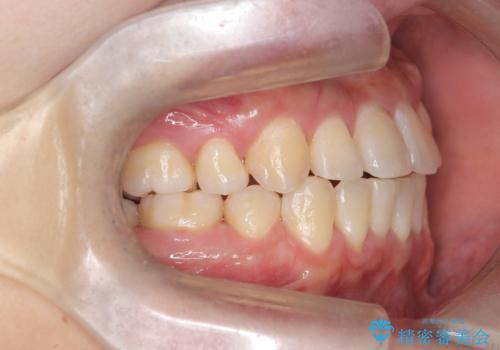

【重度叢生ワイヤー矯正】きれいな歯並びにしたい

- きれいな歯並びにしたいとの希望を持って来院された患者様です。

上下左右小臼歯を抜歯する治療計画を立て審美装置にて治療を行いました。

骨格的3級傾向もあり、咬合関係を仕上げるのに時間がかかりましたが、患者様には大変満足していただけました。